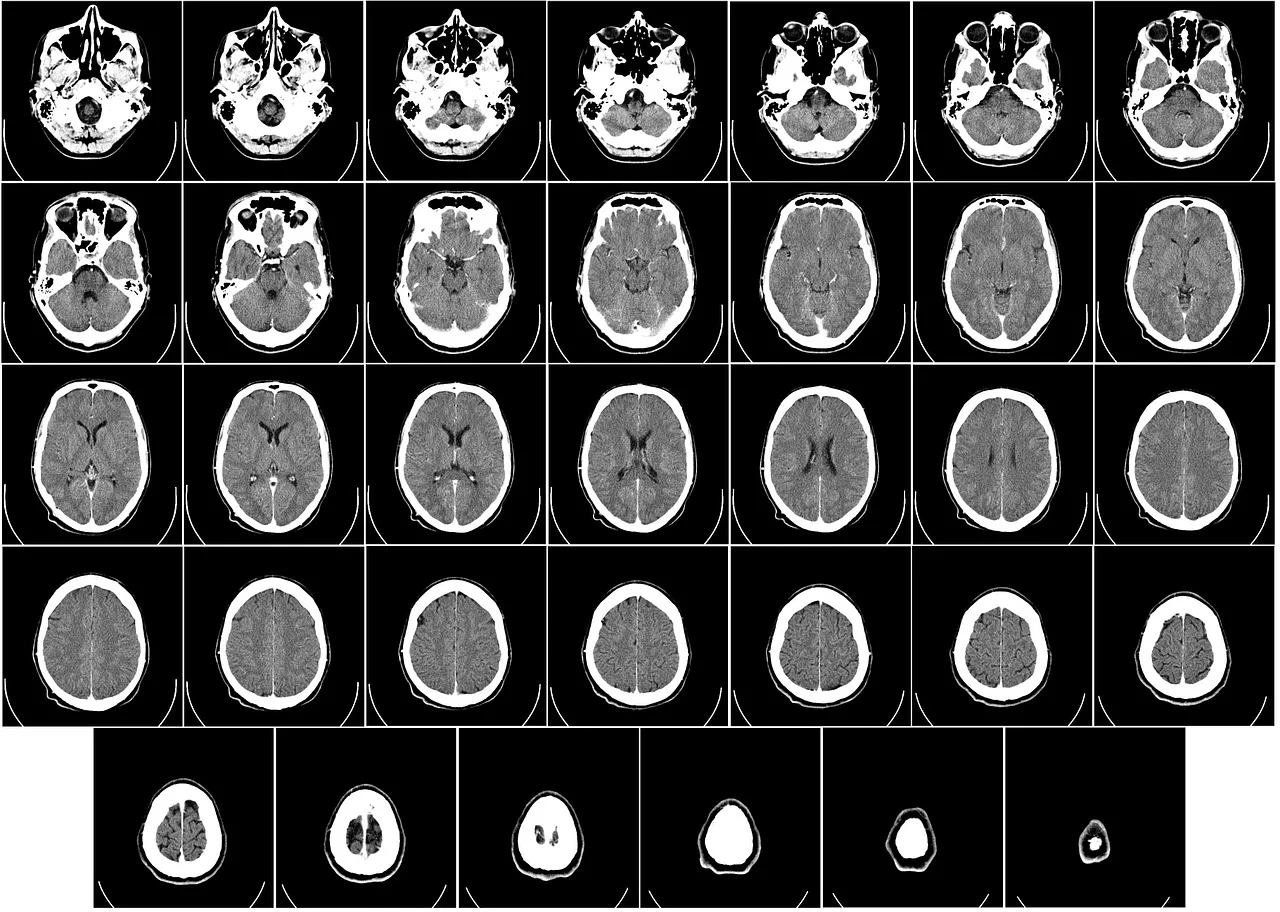

더 나아가, CT(컴퓨터 단층촬영)는 X-ray를 다각도로 촬영한 이미지를 컴퓨터로 재구성하여 단층 이미지를 생성합니다. 이는 종양, 출혈, 장기 손상 등의 정밀한 진단에 유용하며, 응급 상황에서 중요한 역할을 합니다. 하지만 X-ray와 CT는 방사선 피폭량이 상대적으로 높아 반복적인 사용 시 방사선 노출을 최소화하기 위한 관리가 필요합니다.